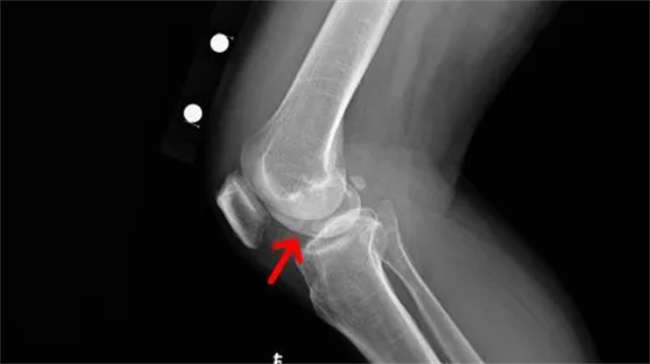

软骨炎是一种关节疾病,其主要特征是关节软骨的退化和磨损。它通常发生在老年人,但也可能影响到年轻人。软骨炎会导致疼痛、僵硬和关节运动受限等症状,严重时会严重影响生活质量。本文将介绍一些治疗软骨炎的方法。...

软骨炎是一种关节疾病,其主要特征是关节软骨的退化和磨损。它通常发生在老年人,但也可能影响到年轻人。软骨炎会导致疼痛、僵硬和关节运动受限等症状,严重时会严重影响生活质量。本文将介绍一些治疗软骨炎的方法。